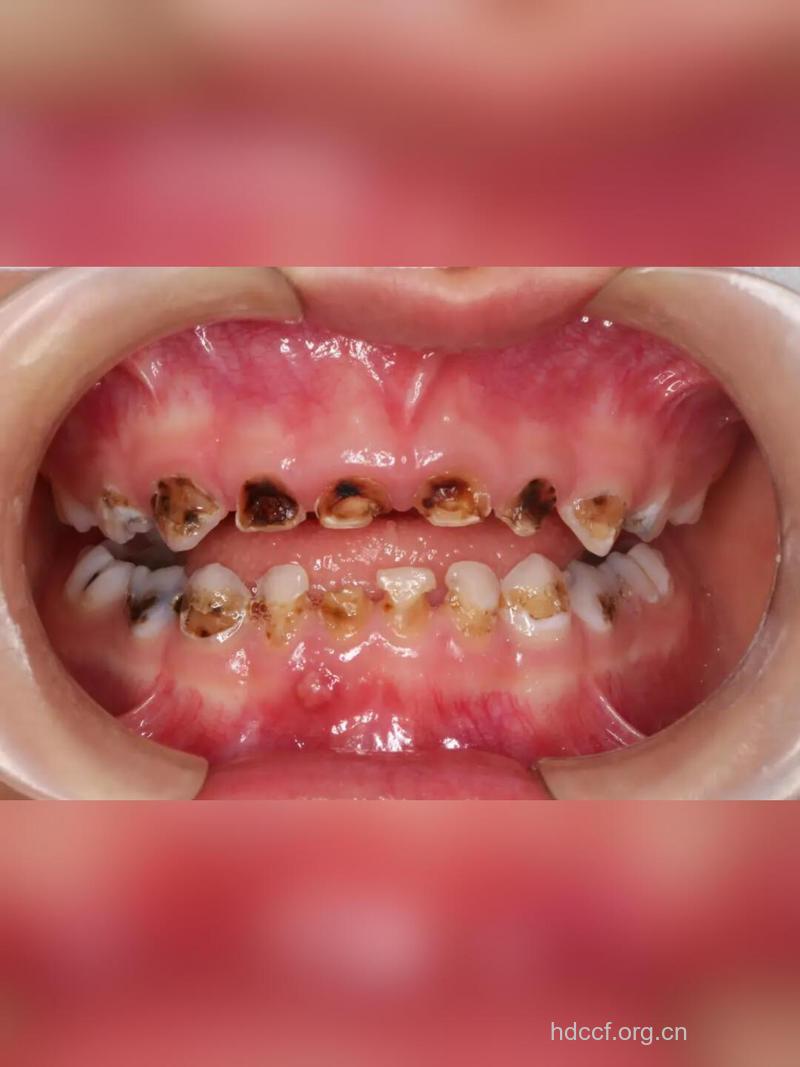

乳牙龋齿是儿童最普遍、最常见的口腔疾病,我们国家5岁儿童患龋率为66%,其中97%未做治疗;12岁儿童恒牙患龋率为28.9%,其中89%未做治疗。

3、儿童睡眠时间长,唾液分泌少,食物残渣容易附着牙面。龋齿初期,患儿没有什么感觉,仅在牙面沟窝、牙缝处出现有黑褐色或灰白色斑块或小窝洞。髓着龋蚀进一步发展,侵蚀了牙本质,会发生冷、热、酸、甜刺激疼痛,当然绝大多数患儿可能没有任何症状。

1、龋齿破坏了牙齿结构,在牙面形成龋洞,容易嵌塞食物,嵌塞后会疼痛不适;儿童乳牙龋坏进一步发展成为牙髓炎、根尖周炎,疼痛剧烈,或者只剩下牙根,反复发炎,影响了儿童的咀嚼和进食,当然也会影响营养吸收和全身发育以及颌骨的发育。

2、乳牙龋坏后,如果没有及时的控制和治疗,龋坏会进一步发展,引起牙髓炎、根尖周炎。除了引起剧烈的牙痛,牙齿根尖周炎还会影响乳牙牙根的正常吸收,阻止牙齿的正常替换,甚至直接影响相应恒牙的正常发育和萌出,临床上表现为乳牙滞留、乳牙早失以及恒牙迟萌、恒牙早萌、恒牙错位萌出等错合畸形。